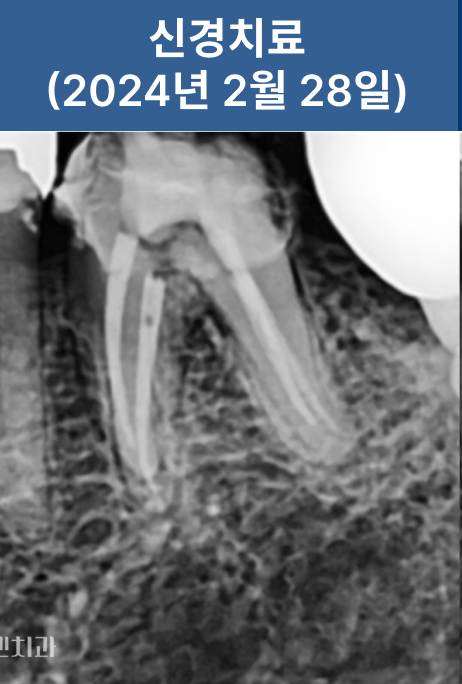

신경치료를 통해 염증 부위를 제거하고,

레진으로 내부를 밀봉한 뒤 크라운을 수복했습니다.

치근까지 염증이 진행되기 전 내원하신 덕분에

발치 없이 치아를 보존할 수 있었습니다.

조기 내원의 중요성이 잘 드러난 케이스입니다.